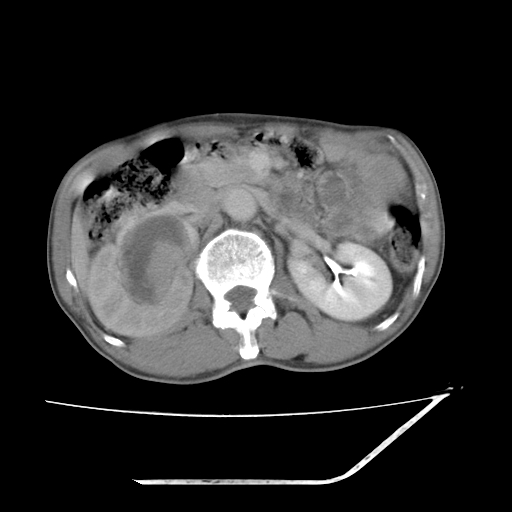

平扫

考虑右肾盂癌,肾动脉受侵,右肾功能减退,右肾盂输尿管积水,管壁增厚,考虑种植转移,应该把下面扫完的

支持右侧肾盂癌伴肾静脉瘤栓形成可能性大,右肾结石.肝右叶后段低密度影,不除外转移.

右肾囊实性占位,支持肾癌,窗宽窗位不是很理想

右肾盂旁ca并肾静脉瘤栓形成/肾功能降低。

右肾结石。

支持 右侧肾盂癌伴肾静脉瘤栓形成可能性大,右肾结石;肝右叶后段低密度影,不除外转移。

1.右侧肾盂癌伴肾盂积水。

2.肾脏功能减退,原因有:(1)肾动脉受侵。(2)肾静脉受侵(3)肾积水,等。本例,肾动脉显影较好,但受压明显;肾静脉无明显显示,受压或静脉癌栓,下腔静脉腔内未见明显充盈缺损。